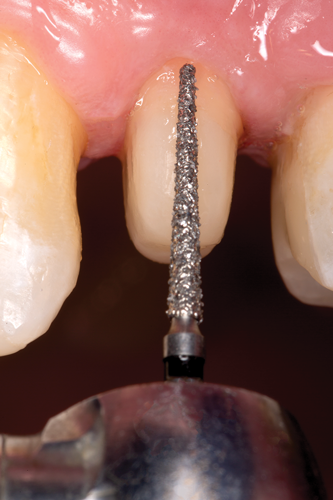

After completion of the endodontic treatment and crown lengthening to develop an ideal ferrule effect (Figure 3 through Figure 5) a diagnostic wax-up was fabricated to an ideal coronal preparation geometric shape, dimension, and height for the anticipated final composite core buildup (Figure 6). A clear polyvinyl siloxane (PVS) impression material was injected into a nonperforated tray, placed over the diagnostic wax-up, and then put into a pressure pot with cold water for 5 minutes. This procedure is aimed at reducing the potential for the formation of voids and bubbles in the impression material (Figure 7 and Figure 8). A small opening was made above the tooth to be restored using a tapered diamond bur (6847) (Figure 9). It is important to clean the internal surfaces with a microbrush to prevent silicone debris from integrating into the flowable material. Prior to the restorative procedure, a diagnostic wax-up was fabricated to the anticipated extracoronal contours for development of the final crown (Figure 10).

Fig 9. A small opening was made above the tooth to be restored using a tapered diamond bur; the internal surfaces should be cleaned with a microbrush to prevent silicone debris from incorporating into the flowable material.